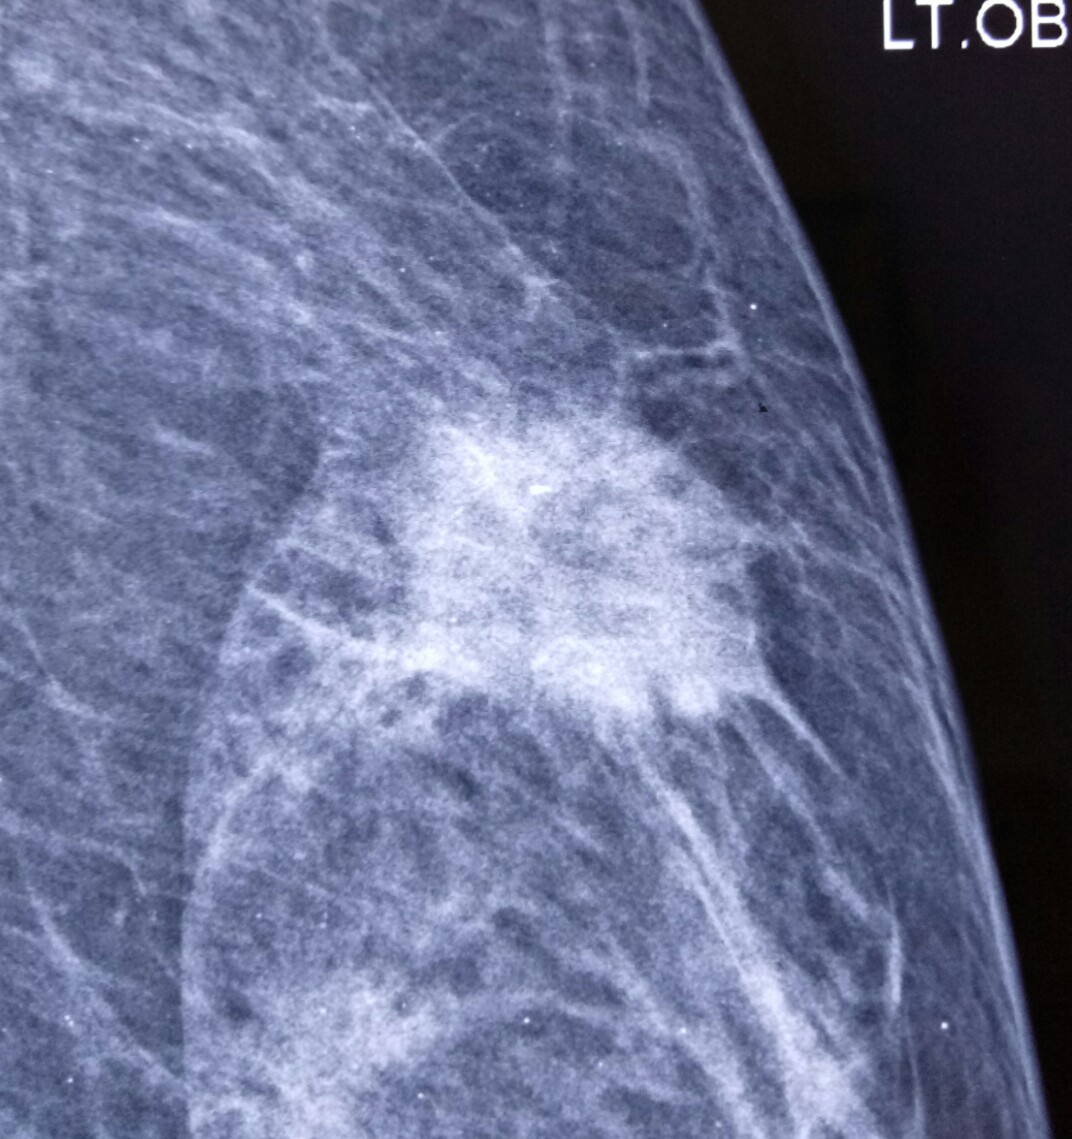

PET scan for breast cancer

Posted on: August 25, 2019

5.1.19

MRM for breast cancer, with PET scan showing axillary mets. 45 years old, c/o dr Jasleen.